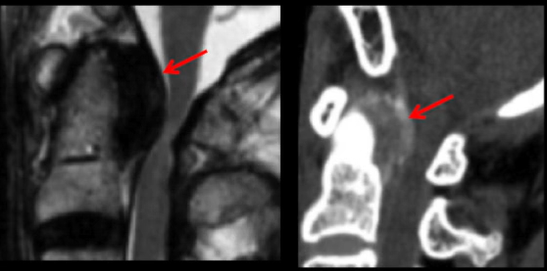

Paciente apresentando dor cervical aguda, principalmente ao engolir. Apresenta os exames de imagem abaixo:

Diagnóstico: tendinite calcificante aguda do músculo longus colli

Pacientes de meia-idade (30-60 anos) / Homem = mulher

Deposito de hidroxapatita de calcio

terapia: NAO OPERAR. Só fazer antiinflamatório e esperar.